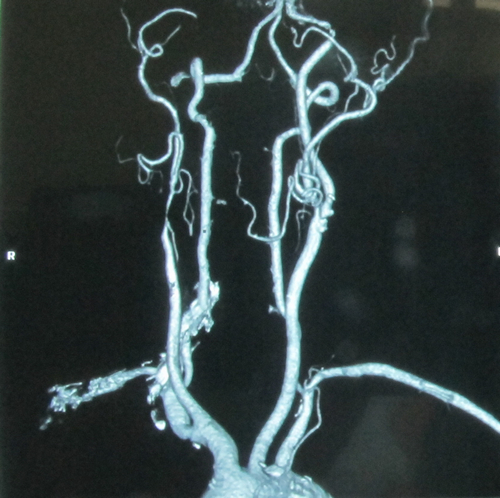

2012年9月24日,北京安贞医院脑卒中中心主任、中美脑中风协作组中方组长张勤奕教授于安贞医院为一例颈动脉狭窄患者实施了颈动脉内膜剥脱术,手术圆满成功。

患者2年前突然出现言语含糊不清,伴左侧口角歪斜,能听懂他人的语言,立即就诊于某医院,就诊途中出现左侧肢体无力,左上肢不能抬起,左下肢不能行走,无肢体麻木、抽搐,查头核磁示“脑梗死”,查颈部血管超声提示“右颈内动脉闭塞”,给予抗血小板、康复锻炼等治疗,症状有改善,可自己行走。2011年患者于外院查DSA提示:“右侧颈内动脉闭塞,右侧颈外动脉狭窄,左侧颈内动脉狭窄”。2011年10月31日患者于安贞医院脑卒中中心行右侧颈动脉成形术,为干预左侧颈内动脉狭窄而再次入院。

入院后行DSA 检查,提示“右颈内动脉闭塞,右颈外动脉中度狭窄,左颈总动脉轻度狭窄,左颈内动脉重度狭窄,左颈外动脉中度狭窄”。

患者心肺功能可,无明确手术禁忌症。2012年9月24日,张勤奕教授于安贞医院为其施行了左侧颈动脉内膜剥脱术,手术圆满成功,患者恢复良好。